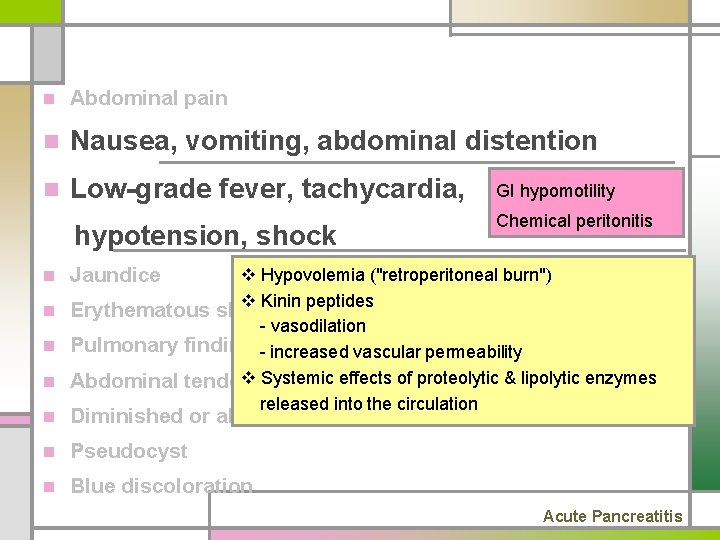

n Abdominal pain n Nausea, vomiting, abdominal distention n Low-grade fever, tachycardia, hypotension, shock n Jaundice n Erythematous skin nodules n Pulmonary findings (atelectasis, pleural effusion) n Abdominal tenderness and muscle rigidity n Diminished or absent bowel sounds n Pseudocyst n Blue discoloration Acute Pancreatitis

n Abdominal pain n Nausea, vomiting, abdominal distention n Low-grade fever, tachycardia, GI hypomotility hypotension, shock Chemical peritonitis n Jaundice n Diminished or absent bowel sounds n Pseudocyst n Blue discoloration v Hypovolemia ("retroperitoneal burn") v Kinin peptides n Erythematous skin nodules - vasodilation n Pulmonary findings- increased (basilar rales, vascularatelectasis, permeability pleural effusion) v Systemic of proteolytic n Abdominal tenderness andeffects muscle rigidity & lipolytic enzymes released into the circulation Acute Pancreatitis